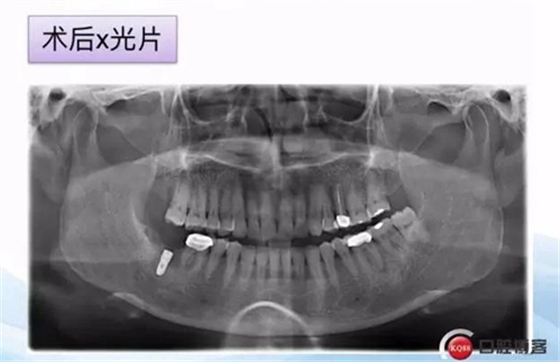

一例后牙常規(guī)種植病例 科貿(mào)嘉友收錄